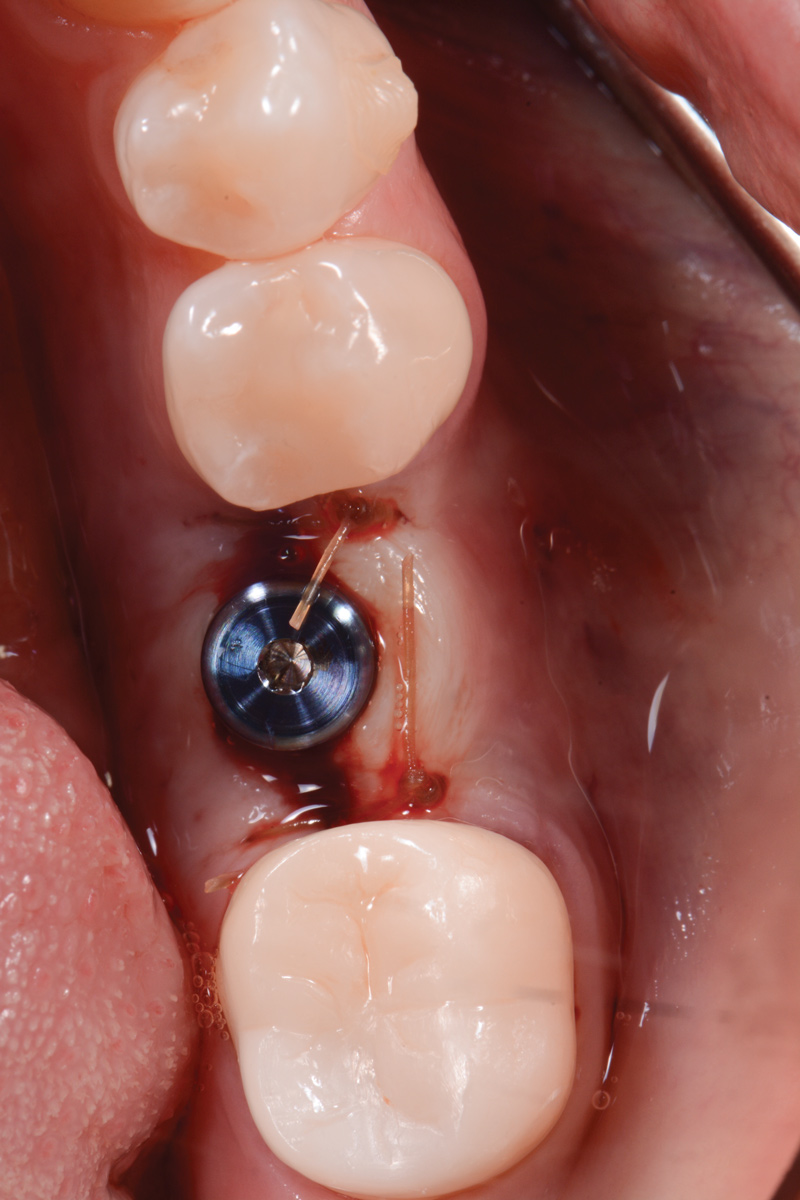

Three months later, the patient was scheduled for second-stage surgery to place a healing abutment. When asked, the patient stated that she had no changes in her medical history. Following local anesthesia infiltration, a crestal incision was made and a full-thickness flap was elevated in the No. 19 area to expose the implant cover screw. A healing abutment measuring 5 mm x 5 mm was placed, and two single interrupted resorbable sutures were used to close the flap.

The following day, the patient presented for an emergency, reporting she began to bleed after she left the office and had continuous bleeding that day and night. Vital signs were normal (blood pressure was 115/65 mmHg, and pulse was 53 beats per minute). The first attempt to control the bleeding included having the patient bite on wet collagen wound dressing and alternate using wet- and dry-gauze compression for 30 minutes. After the removal of the collagen wound dressings, the bleeding restarted spontaneously. The sutures were then removed, and a collagen wound dressing was placed under the flap. Two single interrupted sutures were used, and a third suspended suture was placed around the healing abutment to obtain compression in the area. The patient was observed for 1 hour. During this time, wet-gauze compression was used on the area until the bleeding stopped. The patient was then dismissed and told to reapply gauze with pressure if bleeding recurred (Figure 1 through Figure 5).

Fig 1. Second-stage surgery.

Figure 1